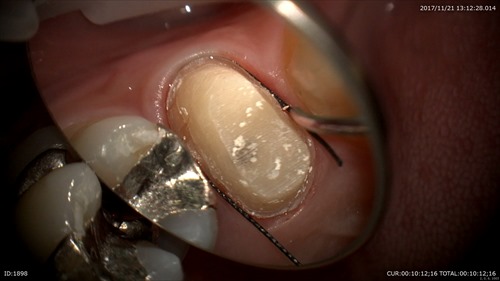

今年も早かったですねー。今年も顕微鏡治療の強化に数多くのセミナーやトレーニングに費やしました。年始から岡口先生や秋山先生のセミナーで顕微鏡の扱い方、アドバンスと非常に充実した1年でした。

2018年の「顕微鏡治療がもたらす恩恵」は今までの治療の質を大きく変え、患者さまの沢山の笑顔と安心を作りました。2019年も顕微鏡治療のさらなる強化、トレーニングを積み患者さまにお返ししたいと思います。

「1本でも多くの歯を保存する事」それが私の歯科医師としての使命。